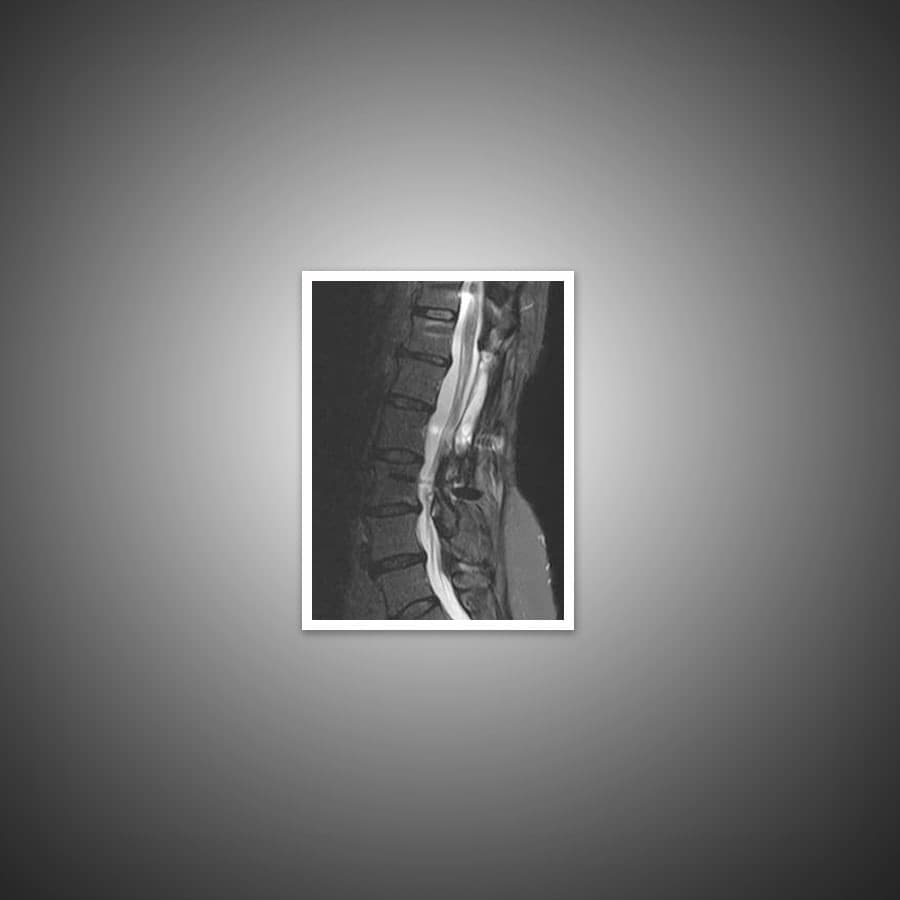

A spinal cord tumor, also called an intradural tumor, is a spinal tumor that that begins within the spinal cord. A vertebral tumor refers to a type of tumor that affects the bones of the spine.

The spine is made of different types of tissues that span the entire length of your back as well as into your neck and pelvis. A tumor can form in almost every type of tissue.

An MRI scan is usually ordered for further evaluation. A combination of chemotherapy, radiotherapy and surgical excision may be required for treatment.